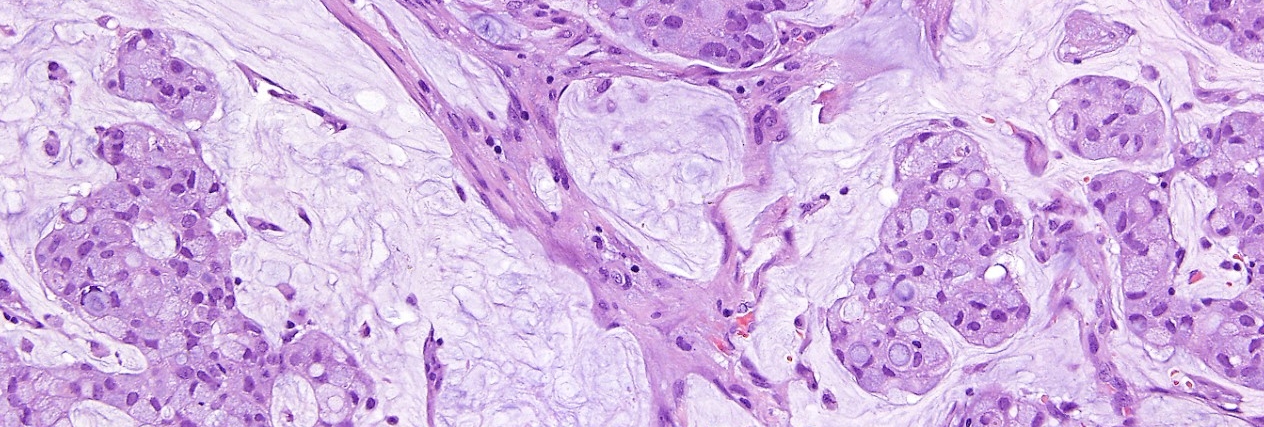

The Anatomic Pathology department provides diagnostic services and specialized testing for patients with solid tumors. Our pathologists are subspecialized and have clinical and research expertise in a range of solid tumors. In addition, our pathologists collaborate with other clinicians to customize each patient’s treatment based on his or her individual diagnosis.

Diagnosis